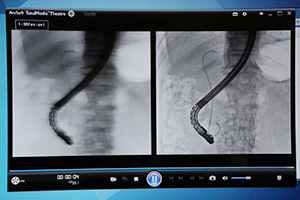

また,X線透視診断装置「CUREVISTA」は,新画像処理エンジン「FAiCE-V NEXT STAGE1」により透視画像処理技術を刷新し,低侵襲治療のより安全で確実な施行を支援する。従来モデルで大きな特長である透視台周辺の広いワークスペースはそのままに,動き追従型ノイズ除去技術“MTNR”や,前後フレームの情報から画像を生成して画像を補完する映像フレームレート補完技術“FRC”により,ノイズを低減してガイドワイヤやステントの視認性を向上させている。加えて,長尺撮影のスロットモードを搭載し,整形外科検査にも対応する。

画像処理技術を刷新したX線透視診断装置「CUREVISTA」 |

補正のない透視画像(左)と新画像処理技術を施した透視画像(右)の比較(CUREVISTA) |